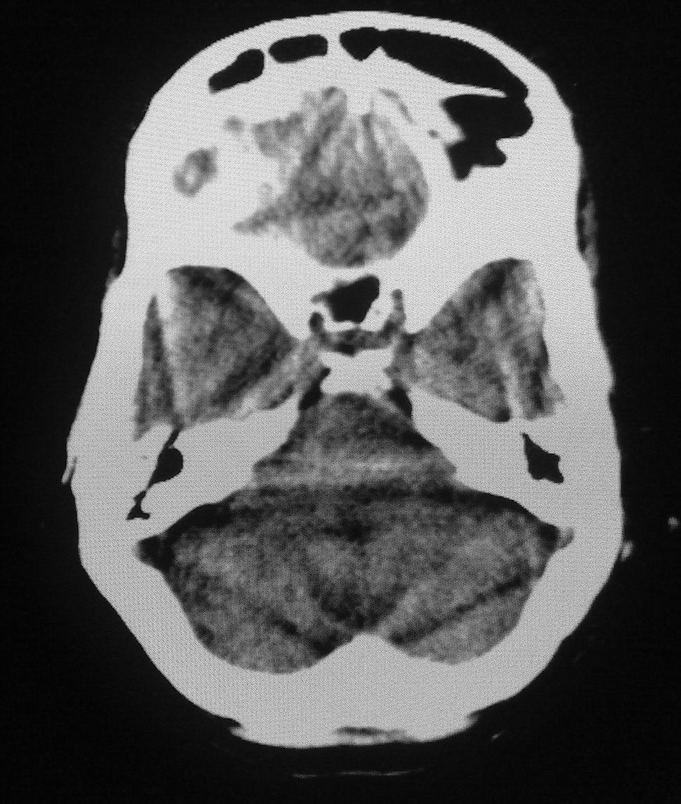

女,46岁,走路有时向一侧偏斜。是小脑萎缩吗?

小脑脑沟增多加深      为小脑萎缩引起的共济失调

小脑脑沟多于四条即为增多,又见加深,所以支持小脑萎缩。

从图像上看的确有轻度小脑萎缩征象,但患者才46岁,有外伤史吗?

小脑萎缩可能性大,建议mri检查。

小脑轻度萎缩